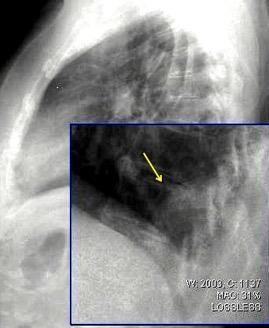

Tumor desmoide (“Fibromatosis agresiva”)

T1: Isointensos con músculos.

T2: Señal intermedia y de alta intensidad.

Presencia frecuente de áreas curvilíneas y lineales dentro de la lesión

Mansour J et al. Diagnostic and Imaging Approaches to Chest Wall Lesions. Radiographics 2022